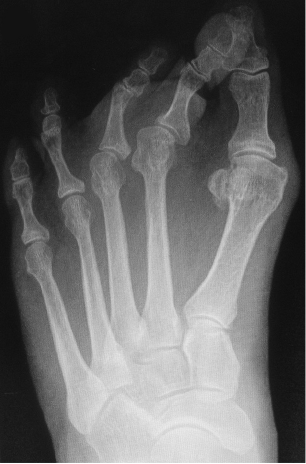

Radiografía convencional

En realidad la placa plantar es radio-transparente, por lo que no se pondrá de manifiesto en una radiografía convencional. Cuando existe evidencia clínica de subluxación MTF, la radiografía estándar es la prueba más práctica para evaluar la congruencia articular. Una radiografía anteroposterior demostrará la desviación transversa del dedo, y la incongruencia o no del espacio articular, así como los eventuales cambios artrósicos intraarticulares. Una radiografía dorso plantar nos ayudará a valorar también la presencia de desviación en el plano sagital y frontal. Los hallazgos más comunes incluyen una interrupción en la parábola del metatarso del pie sintomático, aumento del ángulo entre 1-2 metatarsiano, la desviación medial del segundo dedo del pie y el ensanchamiento de los dedos.